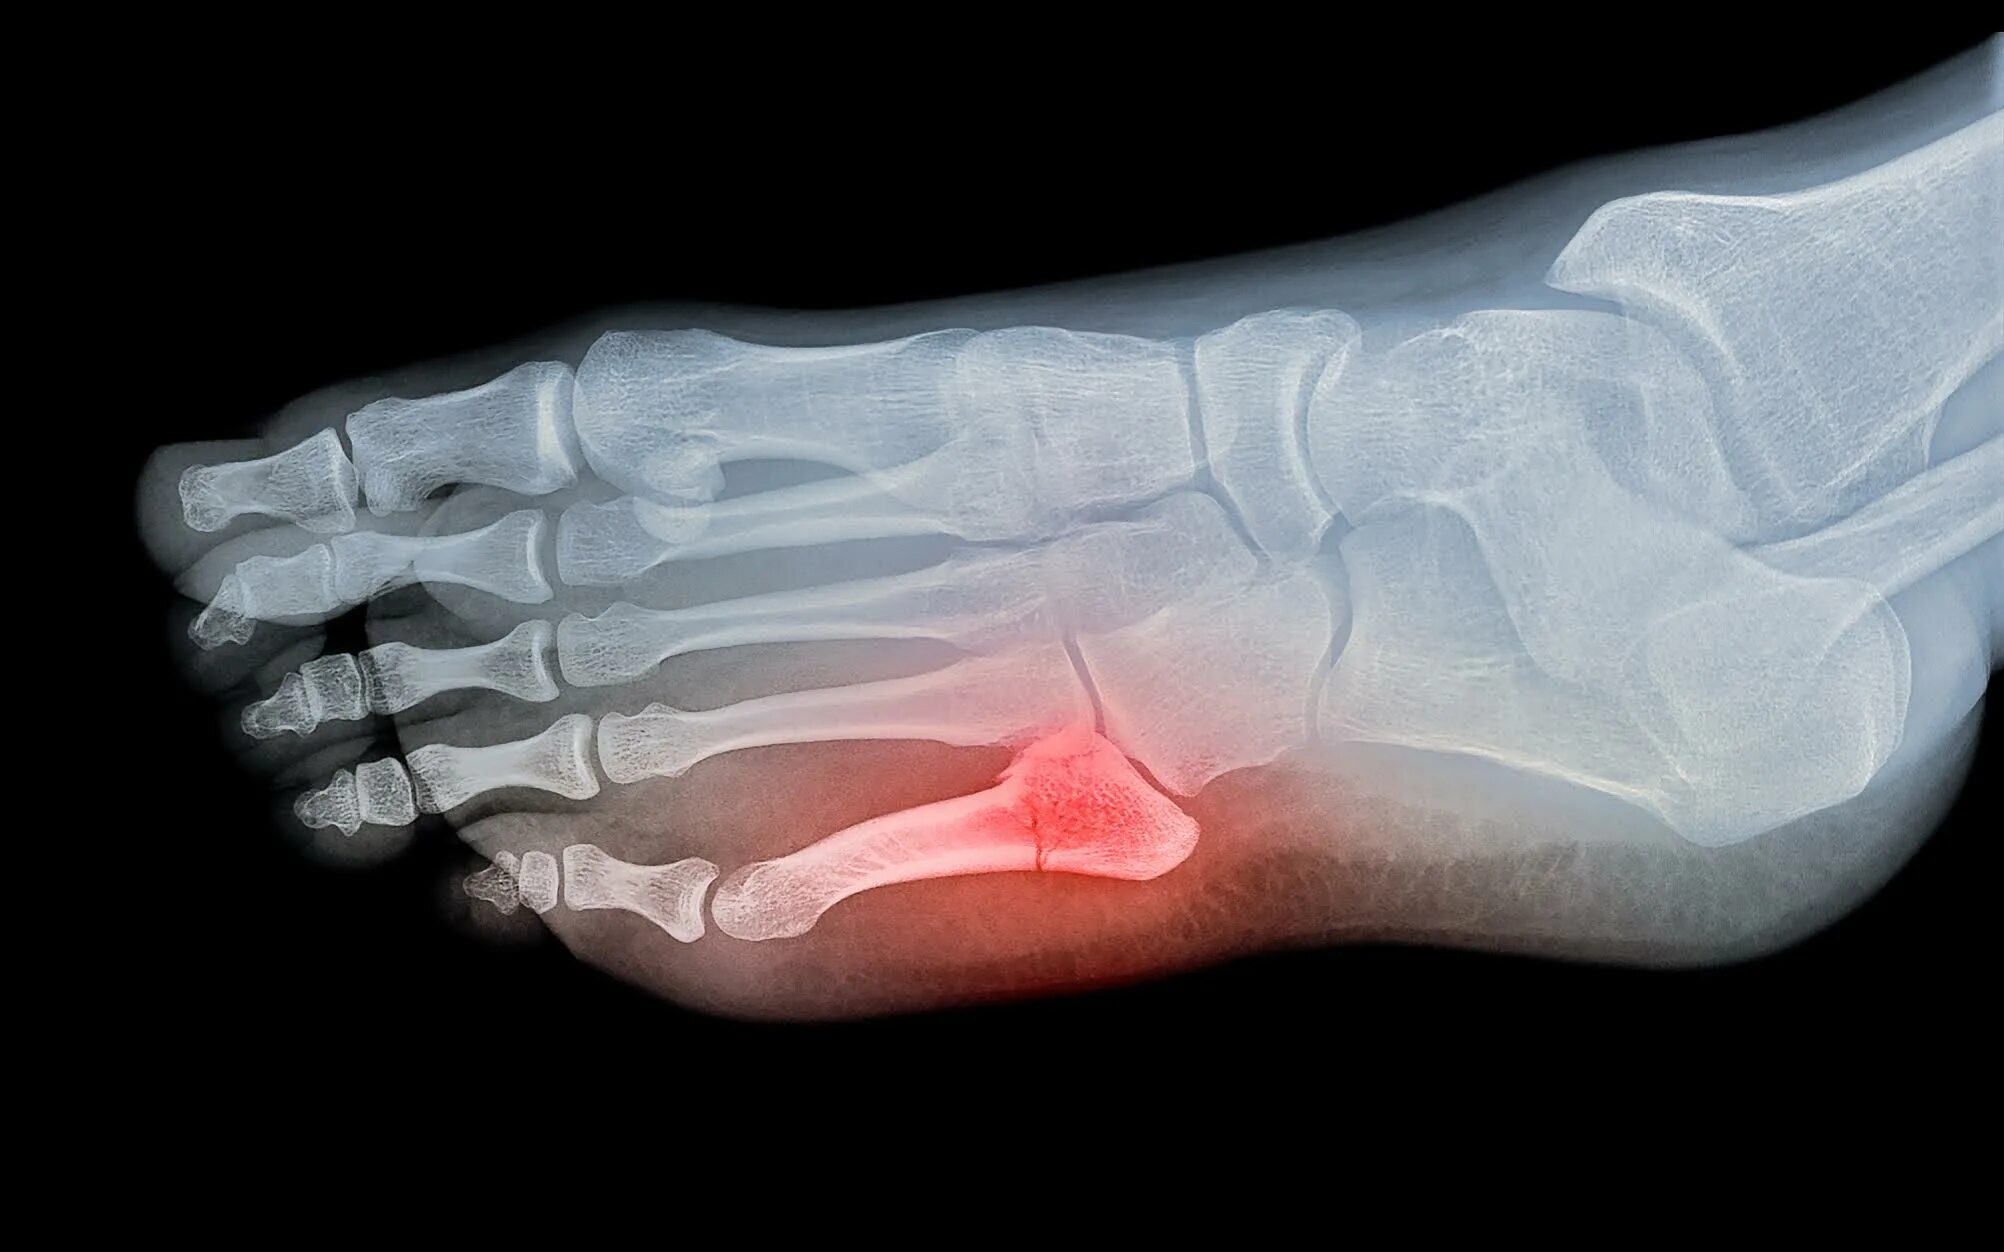

Как определить перелом стопы